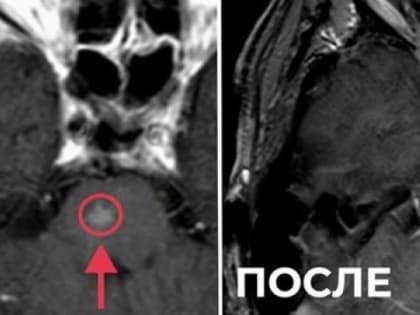

Жителя Владимира избавили от метастаза в стволе головного мозга

Жителя Владимира прооперировали, удалив злокачественную опухоль, с которой он жил более года, сообщил областной минздрав в своих соцсетях.

Во Владимирском онкодиспансере применяют новейшие методы радиохирургии

Фото: минздрав Владимирской области С 2021 года в медицинском учреждении проводят стереотаксическую лучевую терапию пациентам с метастазами в головной мозг,